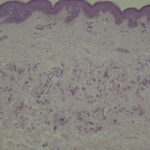

Histopathology. Histologic examination of the involved skin reveals considerable accumulations of swollen and irregularly clumped fibers staining like elastic fibers in the middle and lower thirds of the dermis; that is, they stain deeply black with orcein or Verhoetrs stain . Although normally elastic fibers do not stain with routine stains such as hematoxylin-eosin, the altered elastic fibers in pseudoxanthoma elasticum stain faintly basophilic because of their calcium imbibition. Staining for calcium with the von Kossa method also shows these fibers well. |

Differential Diagnosis. Solar elastosis, like pseudoxanthoma elasticum, shows abnormal elastic tissue. However, in solar elastosis, this material is located in the upper third of the dermis and is present as dense masses rather than as individual altered fibers. Furthermore, these dense masses always show negative staining for calcium. If associated with a perforation, calcific elastosis is easily distinguished from pseudoxanthoma elasticum. In the absence of a perforation, the two are indistinguishable, and clinical data are necessary for differentiation. |